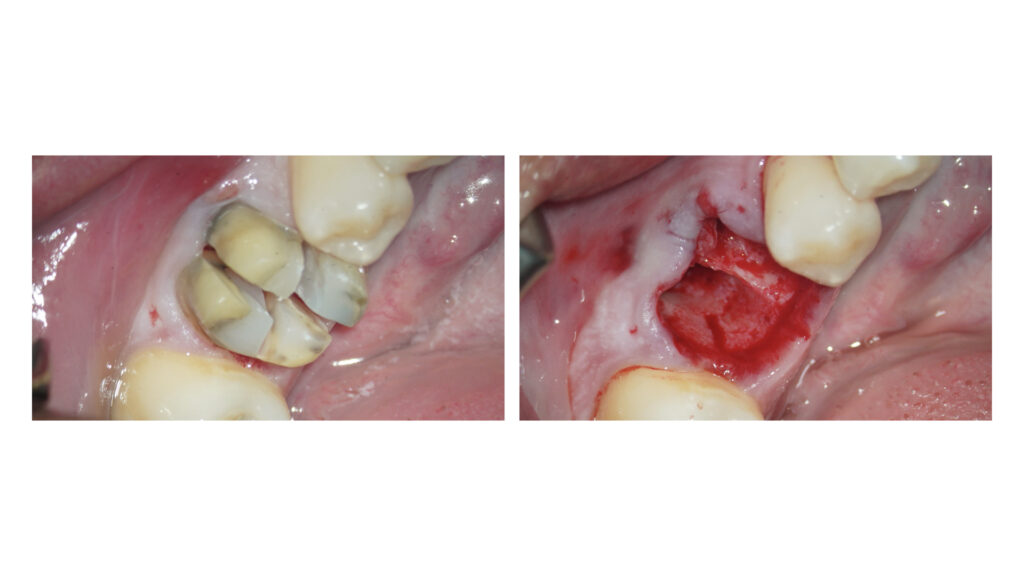

歯周ポケットは深く歯根破折のため抜歯判定となりました。

インプラント治療に向けたGBR(骨増成)およびソケットプリザベーションをCytoplast TXT-200を用いてオープンバリアメンブレンテクニックにて行いました。

メンブレン設置に向けてエンベロープ形成を事前に行なっています。